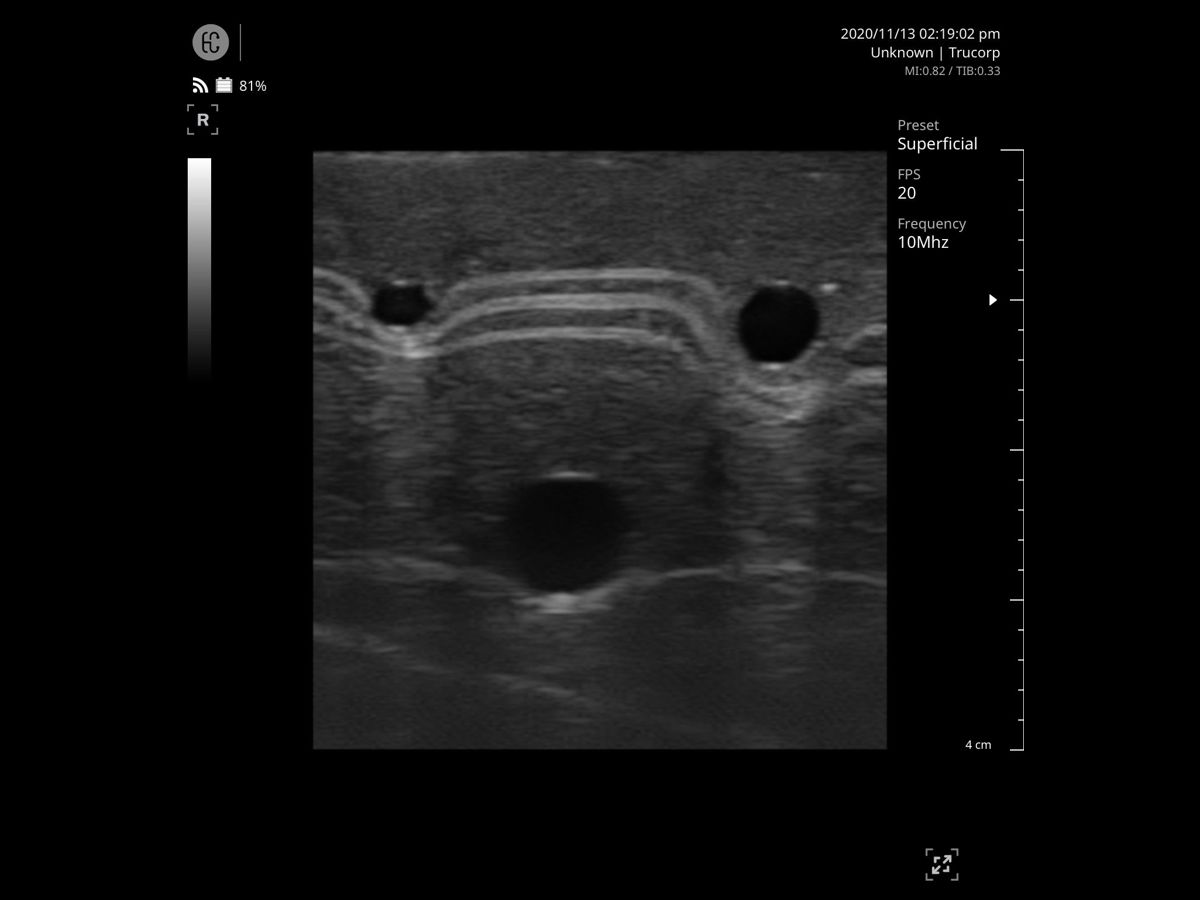

The manufacturer recommends using a size 20G needle for intravenous cannulation. While you can use any appropriate needle for practice, do not use anything larger than 18G, as this may damage the model and void your warranty.

- Prime with artificial blood – prepare approximately 200ml of concentrated blood (available separately) and fill the two vein compartments as per the user manual

- Apply ultrasound gel – apply gel to the block and/or probe as required